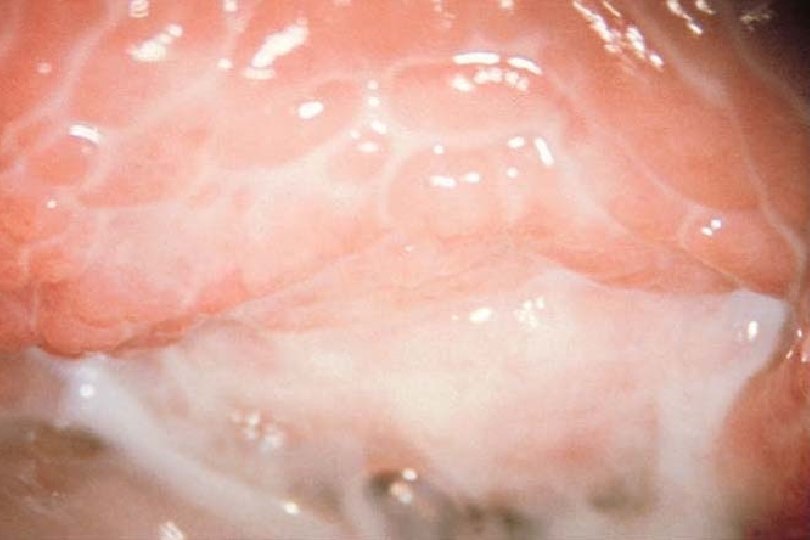

Bacterial Vaginosis Wet Prep: Clue Cell Vaginal Discharge